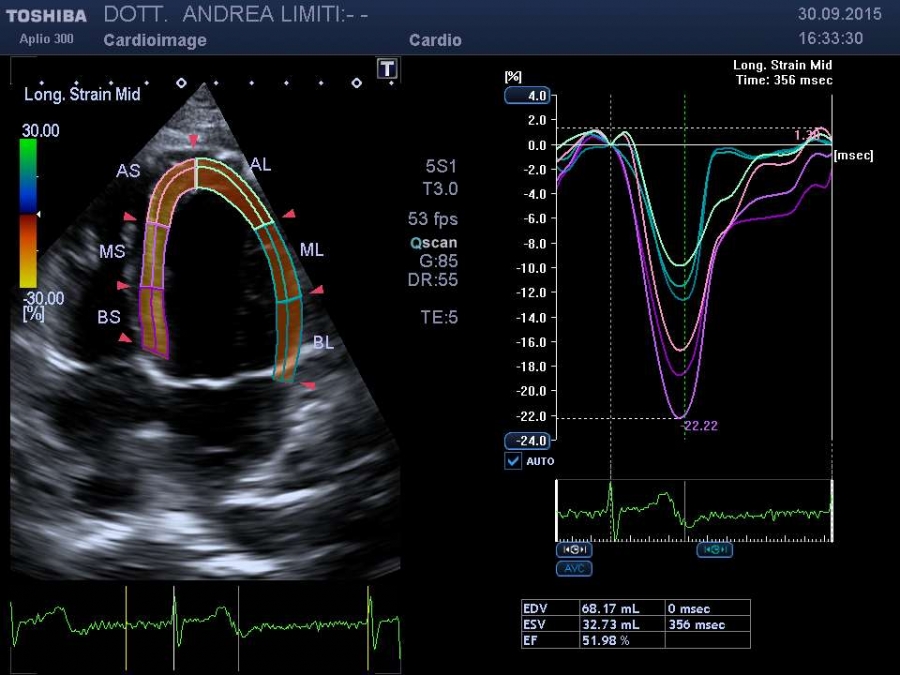

La visita cardiologica, l’Elettrocardiogramma e l’Ecocardiogramma bidimensionale Color Doppler transtoracico consentono di acquisire una ricchezza di informazioni sullo stato anatomico e funzionale del cuore di livello molto elevato che spesso consentono un primo accurato inquadramento dei problemi cardiologici del paziente. E’ importante tuttavia sapere che, anche con gli apparecchi più avanzati, l’ecocardiografia non offre una valutazione diretta dello stato delle coronarie e quindi l’esame non può essere discriminante per la valutazione di sospetti dolori cardiaci.